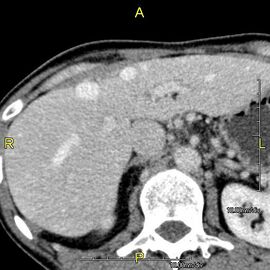

تصوير مقطعي محوسب يظهر كبد شخص بالغ في المستوى المحوري.